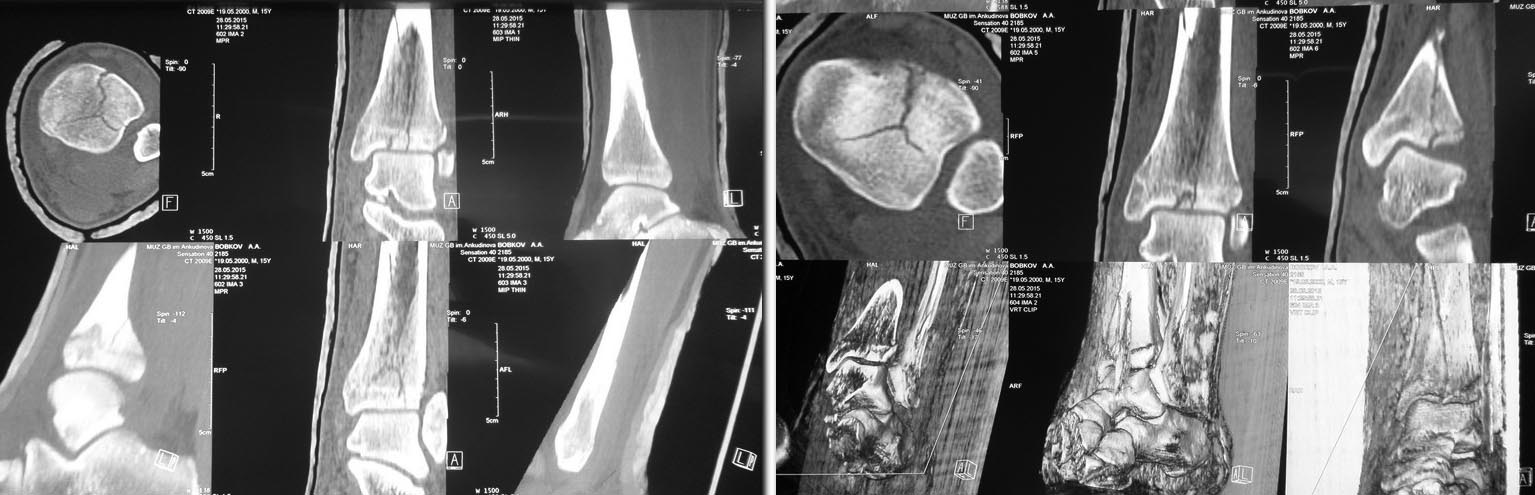

Уважаемые коллеги, представляю вашему вниманию клинический случай. Молодой человек 15 лет получил травму во время игры в регби. Через 30 минут был доставлен в стационар. Проведена рентгенография, для уточнения особенностей повреждения КТ. Выявлено повреждение типа 43-С1, с распространением перелома на ростковую зону большеберцовой кости. Под наркозом проведена ручная репозиция перелома костей левой голени + гипсовая иммобилизация U-образным глубоким гипсовым лонгетом до средней трети бедра. Сосудистых и неврологических растройств нет. Умереный отёк нижней трети голени. Из анамнеза: хронических заболеваний нет, не курит, серьёзно занимается греко-римской борьбой. Уважаемые коллеги, интересует ваше мнение по поводу дальнейшей тактики лечения. У меня 2 варианта, какой выбрать затрудняюсь. 1. Консервативный в условиях гипсовой иммобилизации, сроком до 3х месяцев. Через полтора месяца заменить длинный гипс на повязку по типу Сармиенто до в\3 голени. 2. Оперативный: MIPO с использованием дистально медиальной большеберцовой предизогнутой пластиноы с угловой стабильностью и винтами по АО.

На первый взгляд, репозиция удалась, но из-за срезанных снимков трудно оценить качество. Без стандартных снимков: прямой, боковой и мортиз, невозможно доказать о репозиции суставной поверхности.

У молодых активных, особенно кто занимается спортом, окончательное решение надо принимать после более тщательного анализа исследований. Надо дополнительные - длинные с вовлечением диафиза и отдельные стандартные снимки, а также повторить КТ!

По снимку варусная версия перелома и такой перелом трудно удержать в гипсе. Иммобилизация в гипсе удлиняет восстановление спортсменов и поэтому желательно оперировать как можно скорее. Надо нейтрализовать варусные силы, иногда медиальным buttress пластиной, но данный вариант более благоприятный, только надо удержать репозицию.

Зафиксировать можно перкутанными винтами, а топографические срезы КТ укажут направление установки винтов. Кортикальные винты 3.5 мм доступный вариант, который даст преимущество в раннем сроке (3 недели) начать движение в суставе!

Сделал КТ контроль. Можно обойтись 3 винтами.В области эпифиза: 1 спонгиозный стягивающий винт провести снаружи кнутри, 2 стягивающий спонгиозный винт спереди назад и немного изнутри кнуаружи. На диафизе 1 кортикальный стягивающий винт. После операции 3 недели гипсовой иммобилизации, после чего рентген контроль и начинать постепенную поэтапную нагрузку на оперированную конечность. Сперва ходить 2 - 3 недели с нагрузкой "контакт с полом" + активное ЛФК с инструктором, затем еженедельно повышать нагрузку на 15% от массы тела, через 6 недель рентген контроль и ходить при помощи трости 1 месяц. Если поставить пластину, то срок консолидации будет такой же, но нагрузку можно давать раньше раньше. Джолдас, можете прокоментировать. Заранее благодарен.